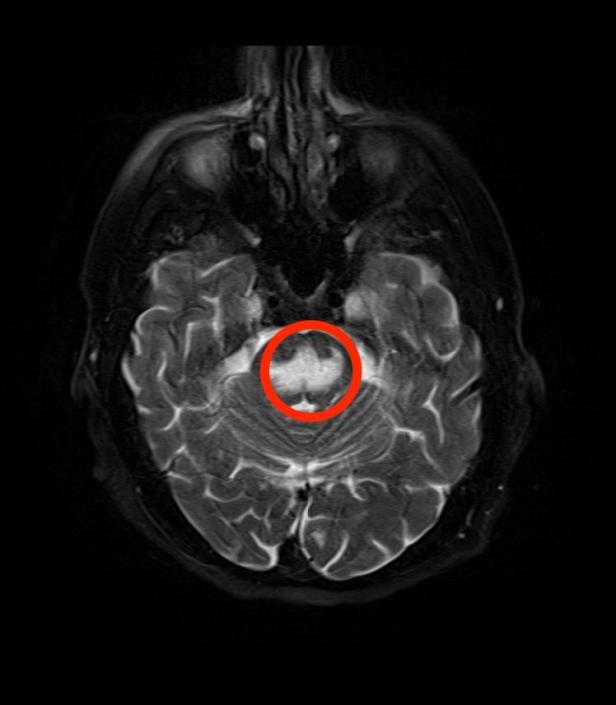

This is specifically relevant in the setting of euvolemic hyponatremia. The maximal rate of correction of the hyponatremia is extremely important and is particularly true in patients with chronic and/or longer duration hyponatremia. Rapid correction of hyponatremia can result in Osmotic Demyelination Syndrome (Central Pontine Myelinolysis), which is an irreversible and severe disorder impairing neurologic function.